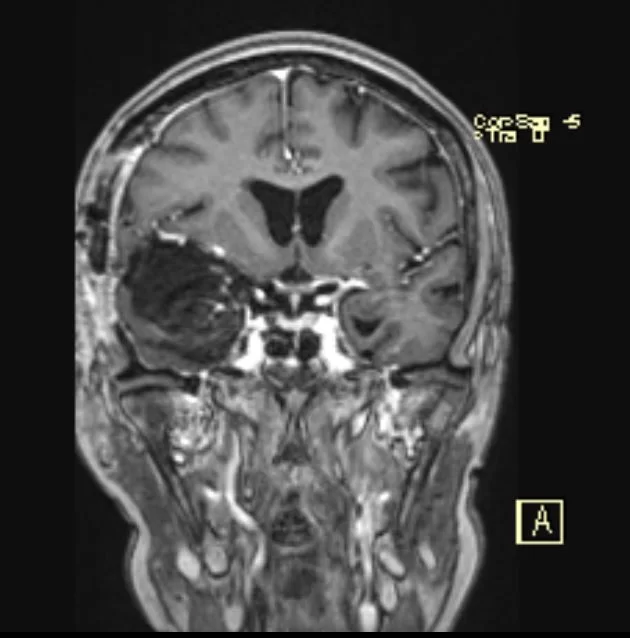

Ο απεικονιστικός έλεγχος με μαγνητική τομογραφία ανέδειξε ευμεγέθη εξεργασία δεξιά, συμβατή με μηνιγγίωμα πτέρυγας σφηνοειδούς οστού.

Πρόκειται για ένα μεγάλο μηνιγγίωμα το οποίο εμπλέκει πολύ σημαντικά ανατομικά στοιχεία όπως την καρωτίδα και τους κλάδους της και το δεξί οπτικό νεύρο.

Σε χειρουργεία σαν και αυτό, πέραν από την αφαίρεση του όγκου, είναι σημαντικό να αναγνωριστούν, να παρασκευαστούν και να διαφυλαχθούν όλες οι αρτηρίες της περιοχής, προκειμένω να αποφευχθεί κάποιο μετεγχειρητικό έμφρακτο. Το οπτικό νεύρο, το οποίο συχνά είναι πιεσμένο, πρέπει επίσης να αναγνωριστεί και φυσικά να αποκολληθεί με προσοχή από τον όγκο.